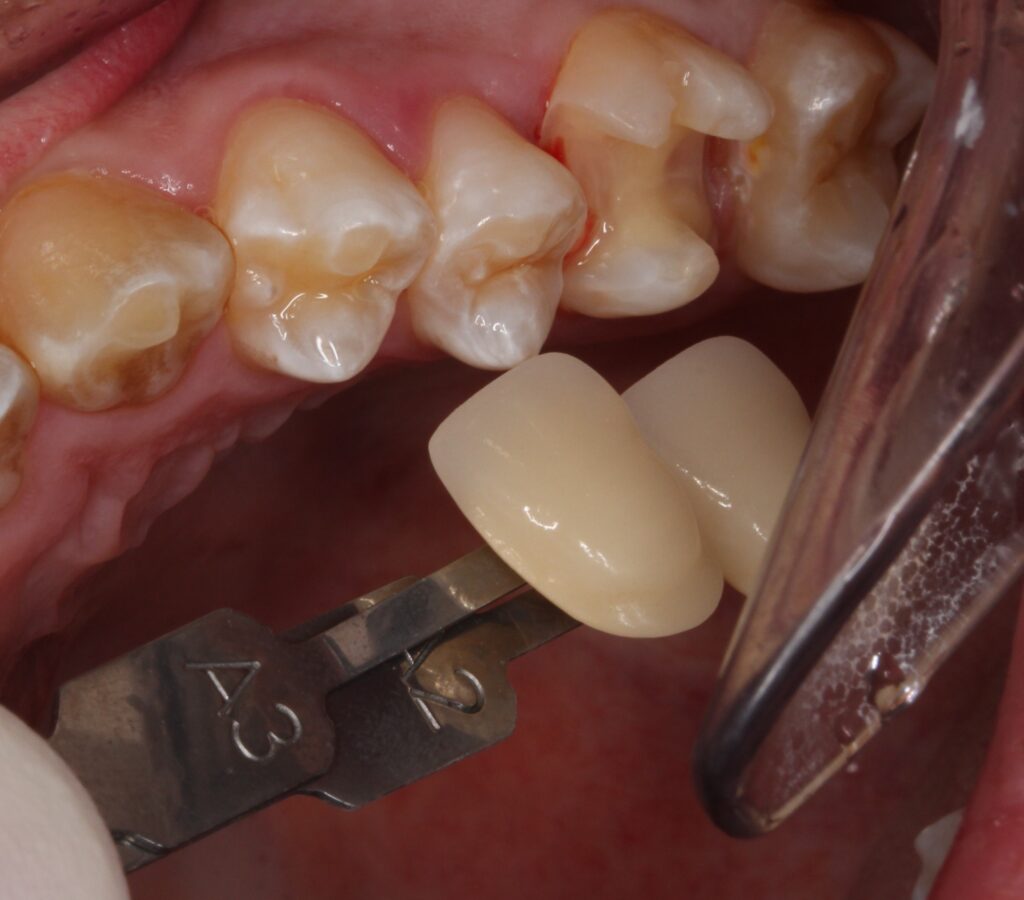

お口の中を見てみると、

青い枠の箇所にセラミックが入っています。一応セラミックなので白い材料で見た目きれいです。

頬っぺた側から見てみると、セラミックと歯の接合部に黄色い付着物があります。

歯とセラミックがずれてついていますし、接着剤がはみ出て固まっています。